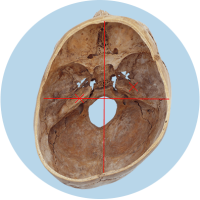

Das größte Problem besteht darin, dass der Kopf in seiner Struktur verändert wird – die Schädelbasis wird schief. Davon sind hauptsächlich die Stellung der Ohren (Gleichgewichtsorgane), die Kiefergelenke (Zahnfehlstellungen) und Halswirbelkörper betroffen. Kritisch wird dies spätestens, wenn sich die Kinder zum Ende des 1. Lebensjahres aufrichten und eine schiefe Wirbelsäulenhaltung entwickeln.

Die verschobene Position der Gleichgewichtsorgane ist durch die roten Kreuze gekennzeichnet.

Fehlerhafte Informationen aus den verschobenen Gleichgewichtsorganen bzw. dem Nackenrezeptorenfeld beeinflussen die Verarbeitung im Gehirn und können zu einer Fehlhaltung der Wirbelsäule führen.